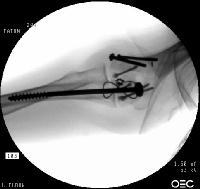

Clinical Example: Transcondylar distal humerus fracture repaired with Herbert screws

Transcondylar distal humerus fractures are usually high energy comminuted difficult fractures, technically difficult to manage. Anatomic reduction, rigid fixation and early motion are desirable, if technically possible. There are a variety of techniques for fixation. Here, Herbert screws were used to secure the two central purely osteochondral fracture fragments to each other and to the proximal humerus.

The olecranon osteotomy was closed with a 6.5 mm lag screw and (belt and suspenders) tension band technique.

Click for larger image